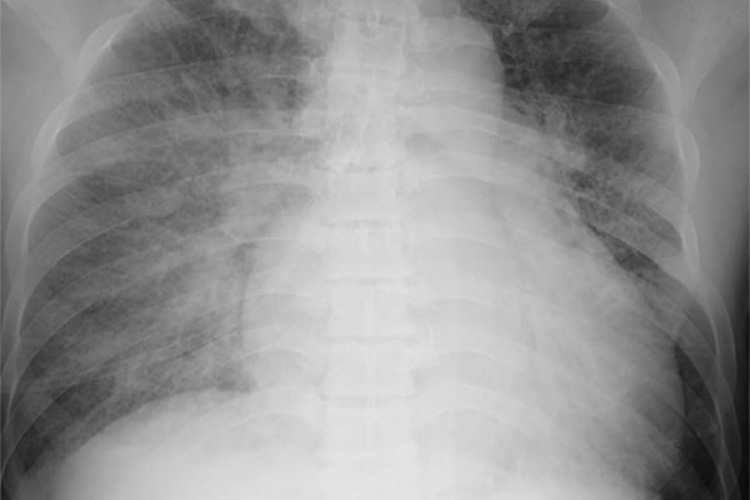

④胸部レントゲン検査

胸部レントゲン検査は状態把握や鑑別診断に有用です。主に肺うっ血や胸水の有無を調べます。広範な心筋梗塞では心不全となり心陰影が拡大します。

肺うっ血の程度は心筋梗塞急性期の予後を左右するため、胸部レントゲン検査は大事な検査です。

また、胸痛や背中の痛みといった症状を起こす病気に大動脈解離という病気があります。胸部レントゲン検査では、大動脈陰影が拡大していないかも確認します。